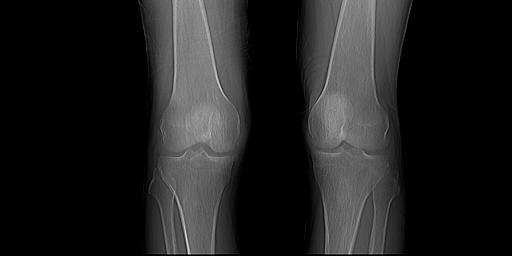

CT51347:男,82 岁,有痛风病史,跌倒致左膝部疼3天

男,82 岁,有痛风病史,跌倒致左膝部疼3天,请会诊。

考虑膝关节痛风性关节炎,退变,关节囊积液,半月板钙化。

膝关节痛风性关节炎,骨性关节炎,骨囊肿,股骨远端不完全性纵型骨折不排除

1)(右/左?)膝关节痛风性关节炎(痛风石形成)。2)(右/左?)膝关节骨性关节炎,伴(右/左?)胫骨上端邻关节囊肿、(右/左?)膝关节内外侧半月板钙化。3)(右/左?)膝关节积液。4)(右/左?)腘动脉钙化。5)(右/左?)膝关节周围软组织肿胀。

支持2楼见解。另:股骨下端后方撕脱骨折不排除。